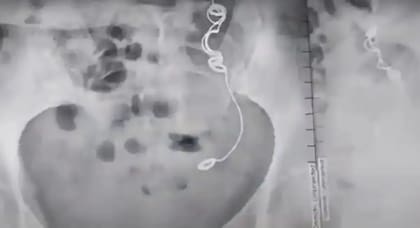

En noviembre de 2022, casi una década después, le ordenaron una resonancia magnética y una ecografía, donde le encontraron una aguja e hilo clavados en su intestino.